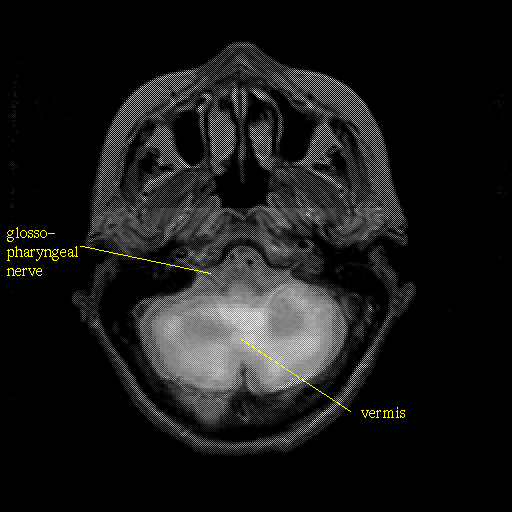

overlay : Slice 11

Slice 11

Pointers

Labeled